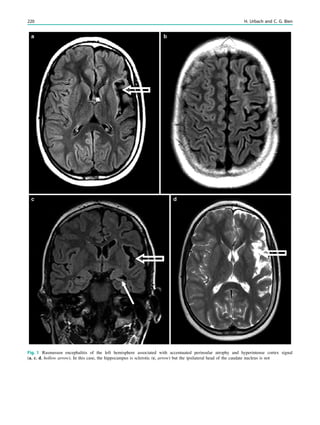

Tuberous sclerosis, 138,145, 165, 167 Type 1 lissencephalies, 132 Type 1, 131 Type 2A, 138 Type 2B, 138 Type I lissencephaly, 131 U Ulegyria, 194, 198, 201 Unprovoked seizure, 26 Urbach–Wiethe syndrome, 174 V Vagus nerve stimulators, 85 Valproate, 252, 253 Varicella zoster, 149 Versive seizures, 11 Vigabatrin, 253 Voltage-gated potassium channels (VGKC), 103 W Wada test, 43, 45, 46 Wake-up seizures, 6 Walker–Warburg syndrome (WWS), 134, 137 West syndrome, 201, 231 Wyburn–Mason syndrome, 185 X X-linked lissencephaly with abnormal genitalia (XLAG), 132 Z Zabramski, 182, 184, 185 270 Index